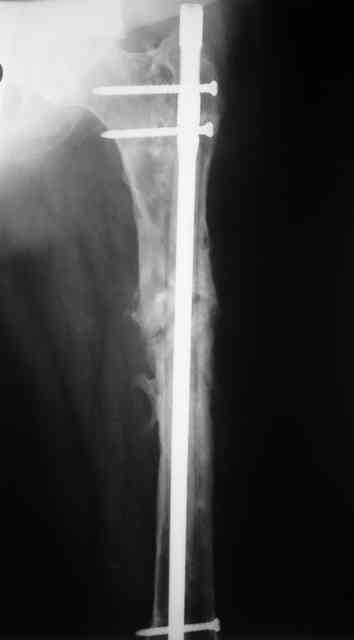

В настоящее время наш пациент ( см. http://weborto.net/forum/1177351385/) ходит с одним костылем. У него периодически открывается свищ на задне-наружной поверхности бедра с умеренным серозно-гнойным отделяемым. Температура тела и анализы нормальные. На рентгенограммах имеются признаки консолидации ложного сустава.

Иллюстрации:

1, 2, 3, 4 - рентгенограммы бедра от 8 августа этого года (через четыре месяца после операции);